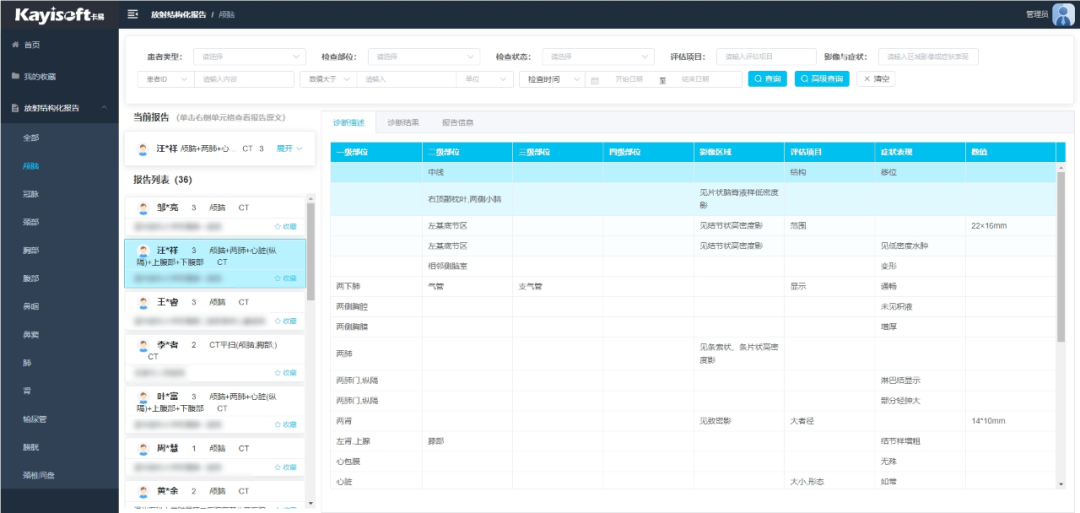

基于AI影像辅助诊断结果,影像云可自动生成结构规范、内容准确的影像检查报告。这不仅有助于医疗机构规范报告管理,还能显著提升医生撰写和审核报告的效率。

基于海量医学数据和影像特征,可以提供诊断建议和相似病例参考,可以整合患者的影像、病理等多模态数据,进行综合分析,为医生提供更全面、精准的诊断依据。可以自动比对患者治疗前后的影像,例如化疗前后的肿瘤大小变化、放疗前后的病灶密度变化等,量化病灶变化,辅助医生评估治疗效果。

智能影像质控+报告质控

实时监控影像检查质量和报告质量,自动生成质控报告,确保影像数据的准确性和可靠性,从而提高医生诊断的准确性,帮助医疗机构提升管理水平。提供海量影像数据和AI分析工具,助力医疗机构开展临床科研和学术研究。